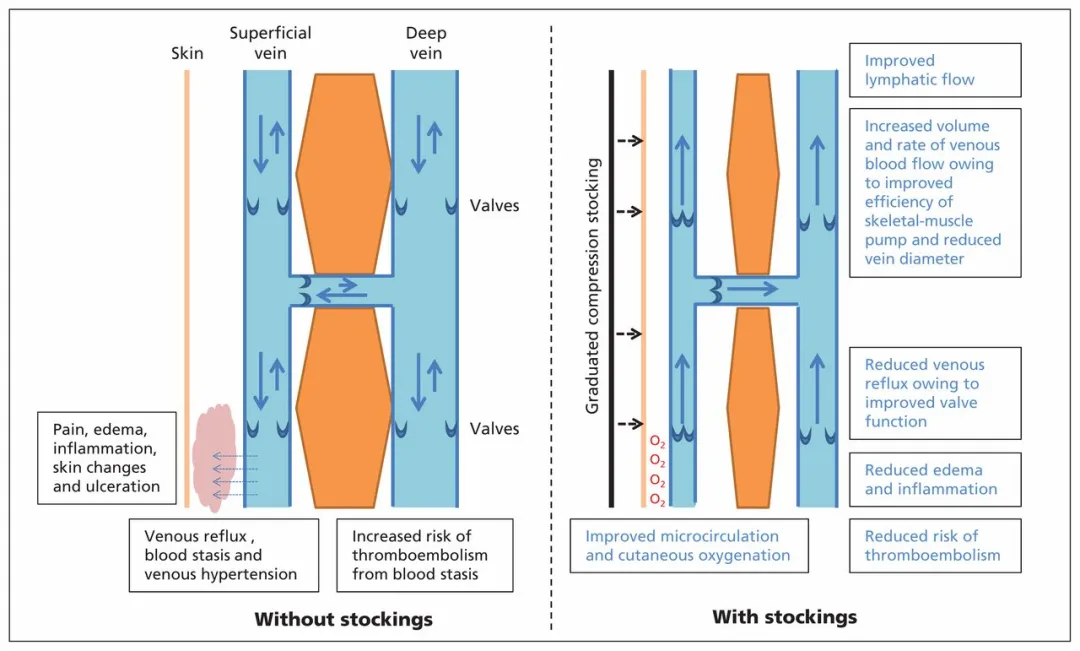

1. 医用弹力袜

关于静脉曲张患者是否要穿用医用加压弹力袜的问题,存在不同意见,一般会推荐穿用。但目前也专家认为梯度加压弹力袜不是静脉曲张的治疗方法,穿梯度加压弹力袜可能会减少静脉反流,但一旦脱下弹力袜,静脉反流又会恢复。

因此,除非患者不能或不愿意进行治愈性干预,否则没有任何病例推荐将它们或任何其他形式的加压作为静脉曲张的治疗方法。只有当静脉曲张继发于血栓后综合症 (PTS) 和/或深静脉功能不全 (DVI) 时,加压才是合适的治疗方法。在这种情况下,所治疗的不是静脉曲张。